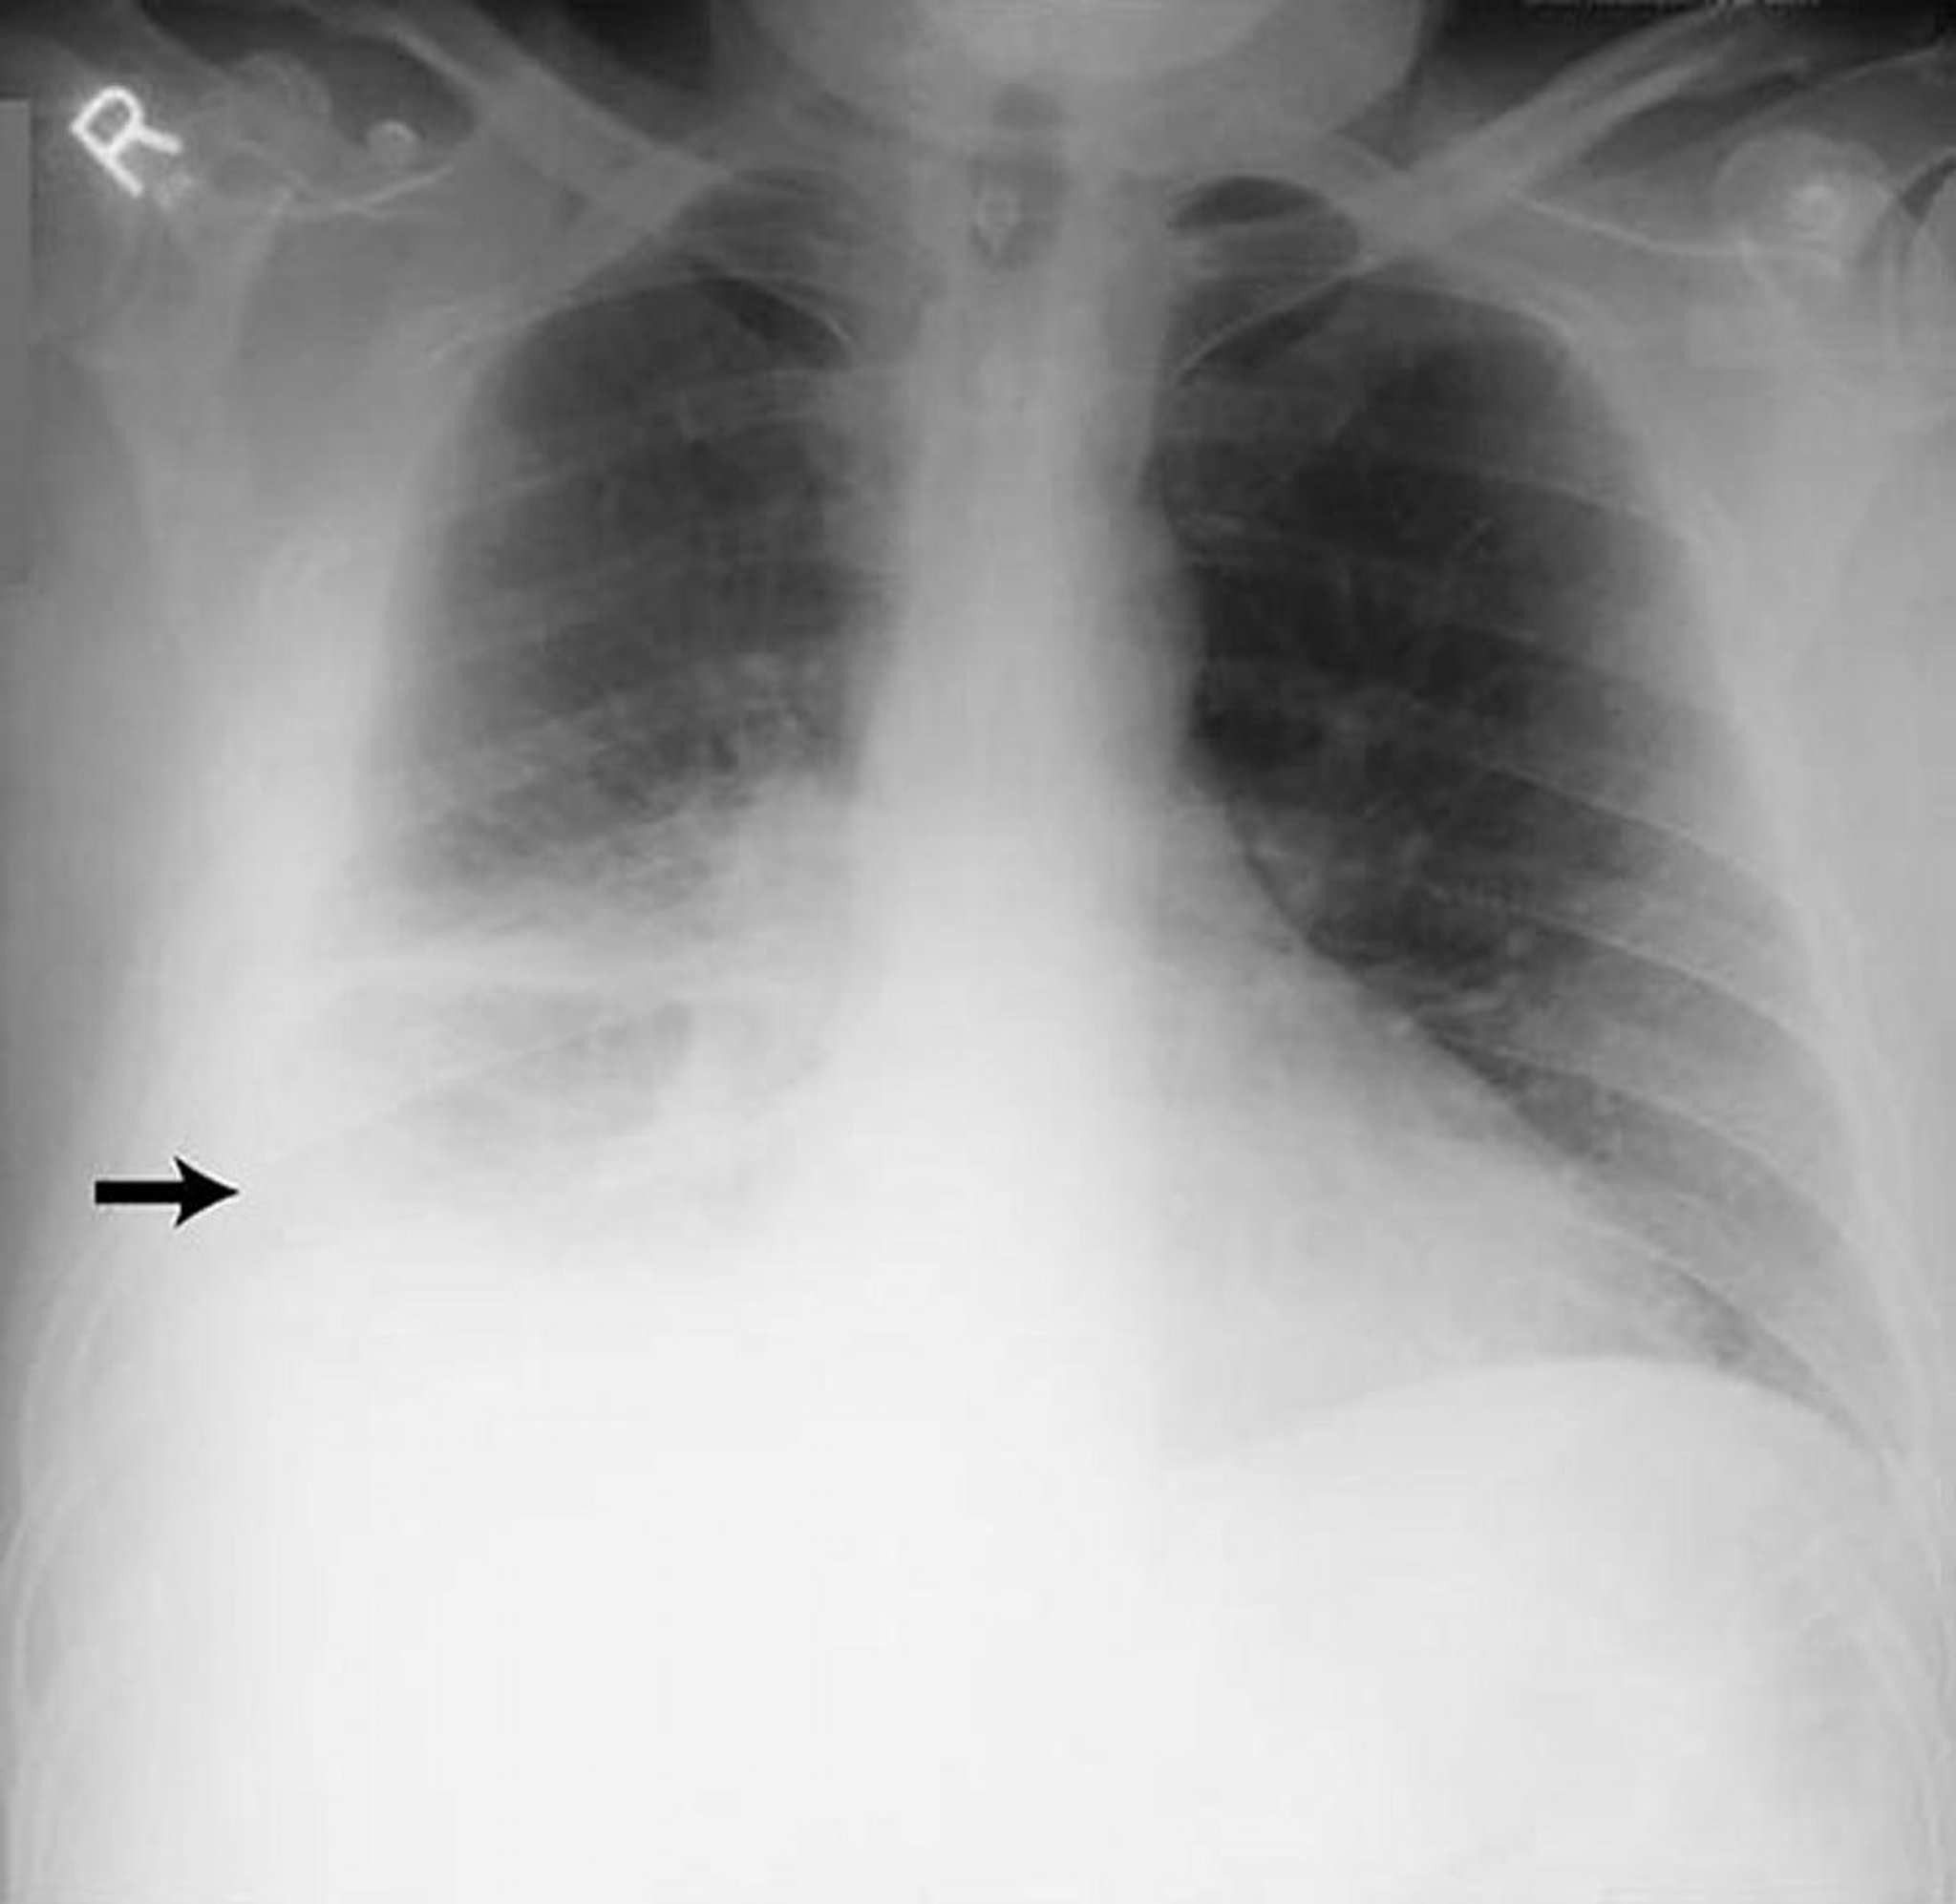

胸水―大量

リウマチ性胸膜炎の患者における大量の右側胸水(矢印)。

By permission of the publisher.From Huggins J, Sahn S.In Bone's Atlas of Pulmonary and Critical Care Medicine.Edited by J Crapo.Philadelphia, Current Medicine, 2005.